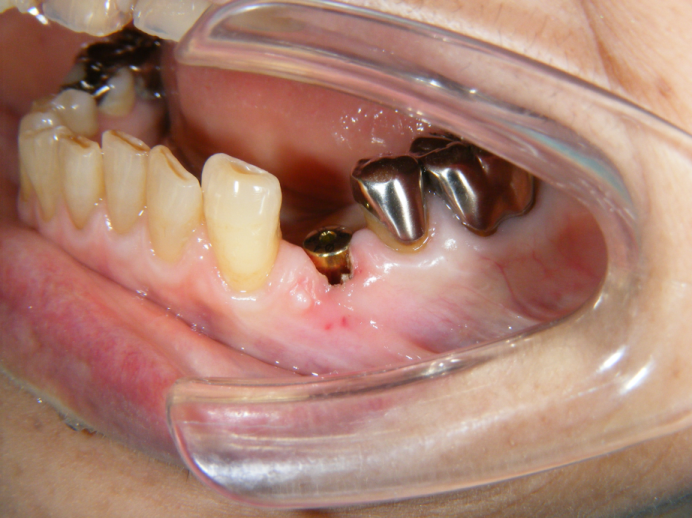

二次オペ

2か月ほど待って、歯肉に隠れているインプラントを見えるようにする

二次オペと言われる処置をします。

ここから2週間待って、型採りを行います。